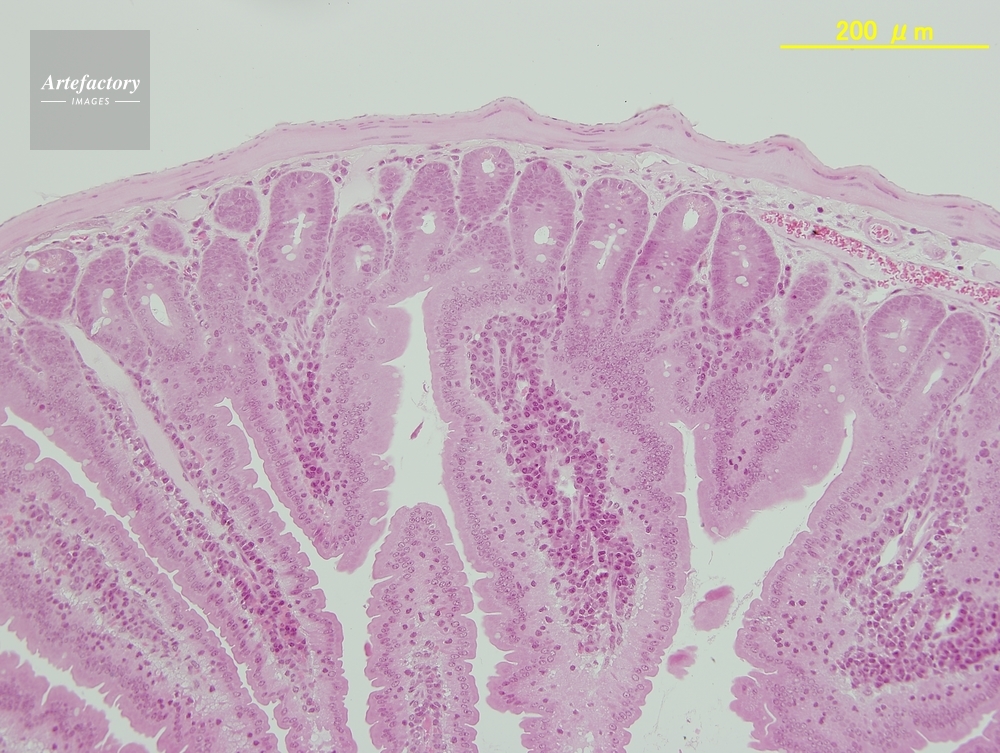

| 作品タイトル | マウス,十二指腸 | モデルリリース | なし | |

| 作家 | OLYMPUS CORPORATION Technolab | プロパティリリース | なし | |